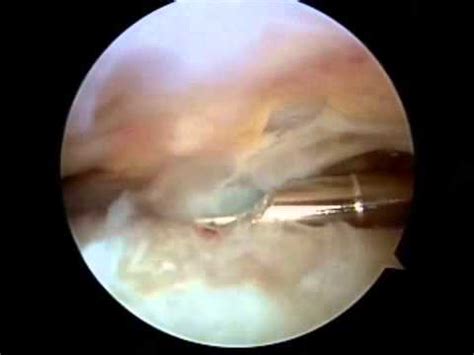

Wat ons onderscheidt: u wordt altijd onderzocht door een orthopeed én een echografist, tijdens hetzelfde consult. Geen doorverwijzing, geen wachten op een apart onderzoek. We stellen de diagnose en behandelen vaak op dezelfde dag.

Dat kunnen we omdat we de beeldvorming zoveel mogelijk in eigen hand hebben. Op de echo, de röntgenfoto of de MRI. Want wij hebben de patiënt onderzocht.

De naam veranderde. Ons hart voor echografie niet. We zeggen het nog steeds dagelijks tegen onze patiënten: Eerst Een Echo.